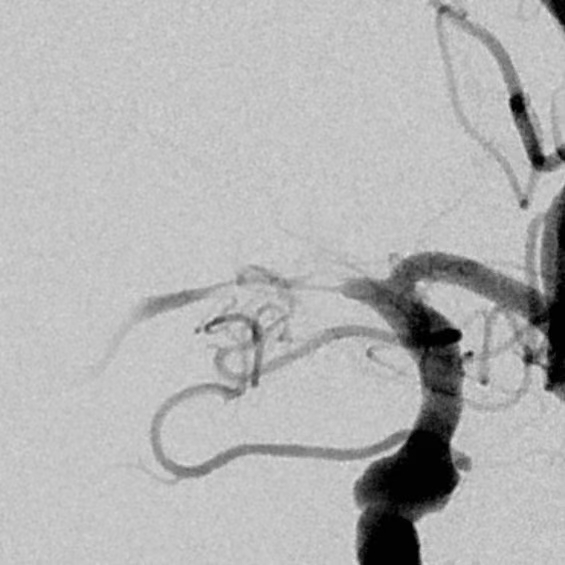

继续药物治疗存在狭窄部位闭塞的风险,果断给予支架植入

支架植入后,重建后血管的形态,血流完全恢复,顺利出院